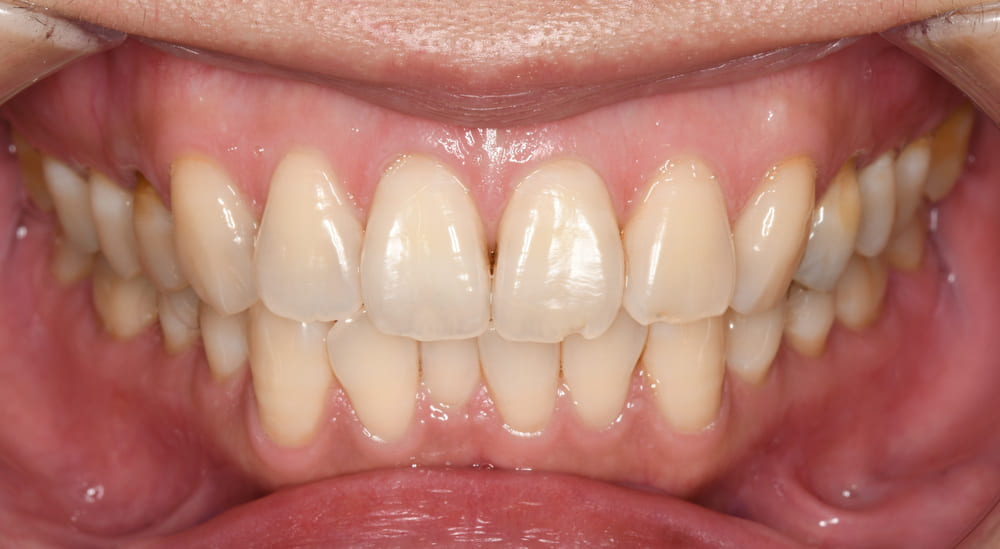

スマイル写真です。

スマイルライン的には正常に近いのですが、上顎前歯が唇側に傾斜して出っ歯感が強いことがお分かりいただけると思います。

とても自然な理想的なスマイルを獲得できました。

スマイル時の出っ歯感も適切に改善され、患者さまも大変満足されておりました。